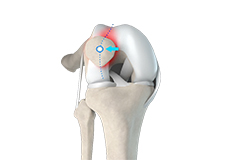

Patellar Instability

Any damage to the supporting ligaments may cause the patella to slip out of the groove either partially (subluxation) or completely (dislocation). This misalignment can damage the underlying soft structures such as muscles and ligaments that hold the kneecap in place.